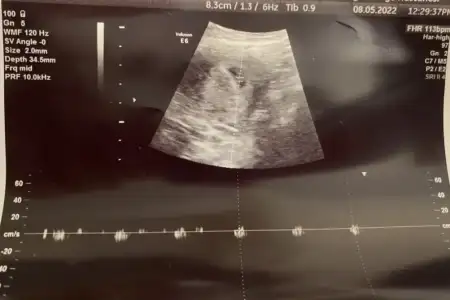

kızlar ah bi de kaç haftalık ve karından mı bakıldığını yazsanızSelamPasha22 pazar göndermiştim erkek gibi demiştin. Dün tekrar gittim yeni görüntü var hala erkek mi

Ay kusura bakma bir öncekinde yazdım ya kafam uçmuş. 6+3 karından. Tekrar ekliyorum fotoyukızlar ah bi de kaç haftalık ve karından mı bakıldığını yazsanız

bu görüntü 7-8 haftalık civarı mıSelamPasha22 pazar göndermiştim erkek gibi demiştin. Dün tekrar gittim yeni görüntü var hala erkek mi

Karışıklık olmasın diye tekrar atayım, ilk görüntü 6+1 pazar günü olan, 2. Görüntü 6+3 salı günü olan ikisi de karından;bu görüntü 7-8 haftalık civarı mıpazar attığın görüntü peki?

seninki prenses canımKarışıklık olmasın diye tekrar atayım, ilk görüntü 6+1 pazar günü olan, 2. Görüntü 6+3 salı günü olan ikisi de karından;